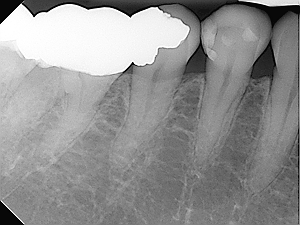

The procedure involves removing the pulp (the live tissue inside the tooth), cleaning and disinfecting root canals and then filling and sealing it.

Most teeth can be saved by endodontic therapy. However, tooth extraction may be necessary if:

• Roots are fractured

• The root does not have adequate bone support

• The tooth can not be restored

• Root canals are calcified and are not accessible